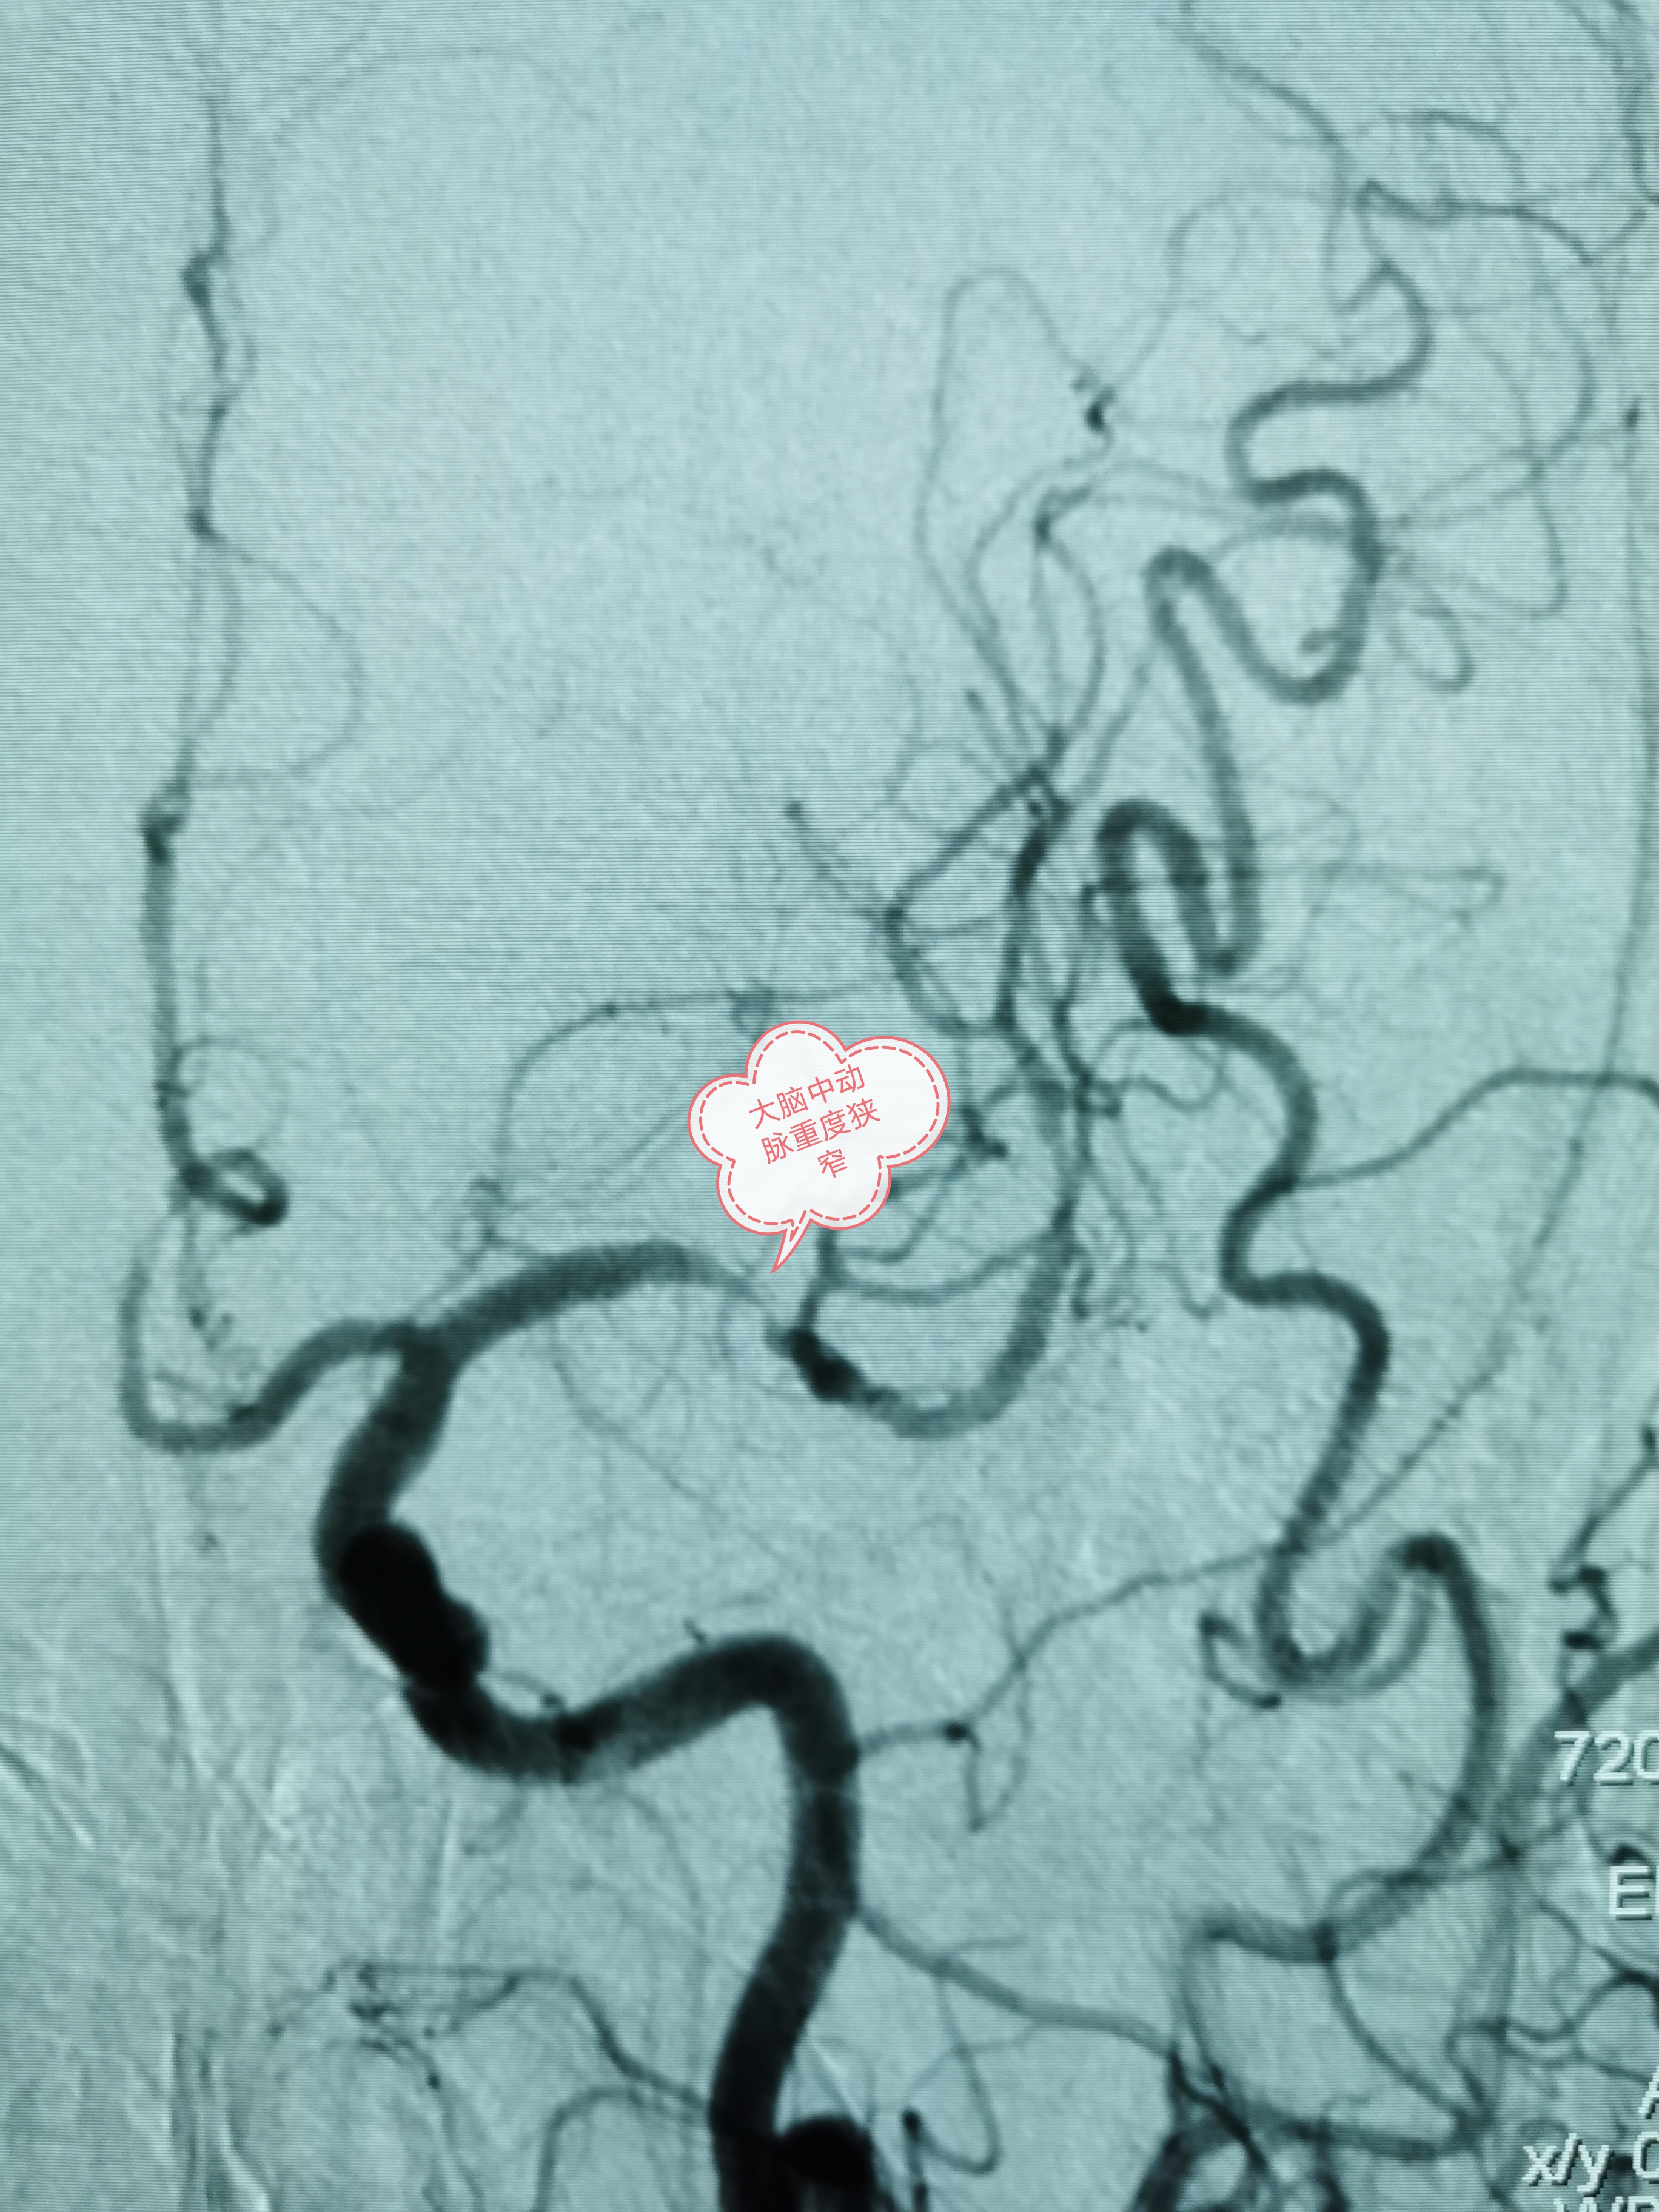

术前左侧大脑中动脉重度狭窄

经过细致的术前准备后,班先生被送入介入导管室进行手术。术中发现班先生右侧颈内动脉一夹层动脉瘤,长14.4mm×高6.2mm,瘤颈宽10.8mm,合并左侧大脑中动脉重度狭窄。韦仕荣主任经过精细操作在患者右侧颈内动脉夹层动脉瘤处置入Tubridge血管重建装置,精确到位,即刻造影可见病变血管的血流形态明显改善。之后在左侧大脑中动脉重度狭窄处予球囊扩张成形术,造影显示血管狭窄明显改善,一次手术解决了两处重大的脑血管病变,手术过程顺利,且无并发症发生。次日班先生即可正常活动,恢复良好,术后第5天即康复出院。